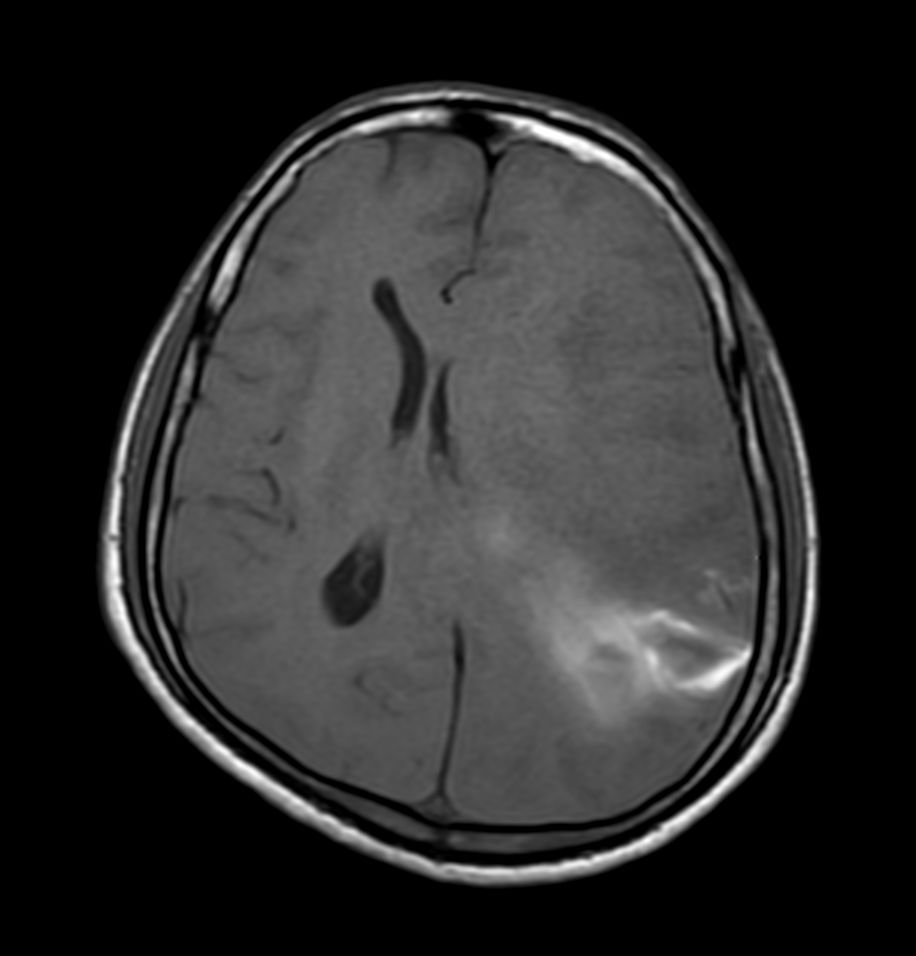

Pediatric Brain with hemorrhagic mass

Pediatric patient with a hemorrhagic mass in the brain